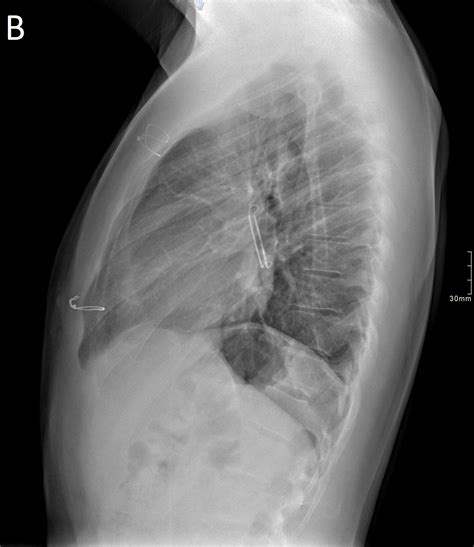

3. Implanting the Device: The closure device, which is typically a small, self-expanding mesh or plug, is deployed at the opening of the left atrial appendage. The device is designed to conform to the shape of the appendage and create a seal.

4. Verifying the Seal: Imaging techniques are used to ensure that the device is properly positioned and that the seal is complete.